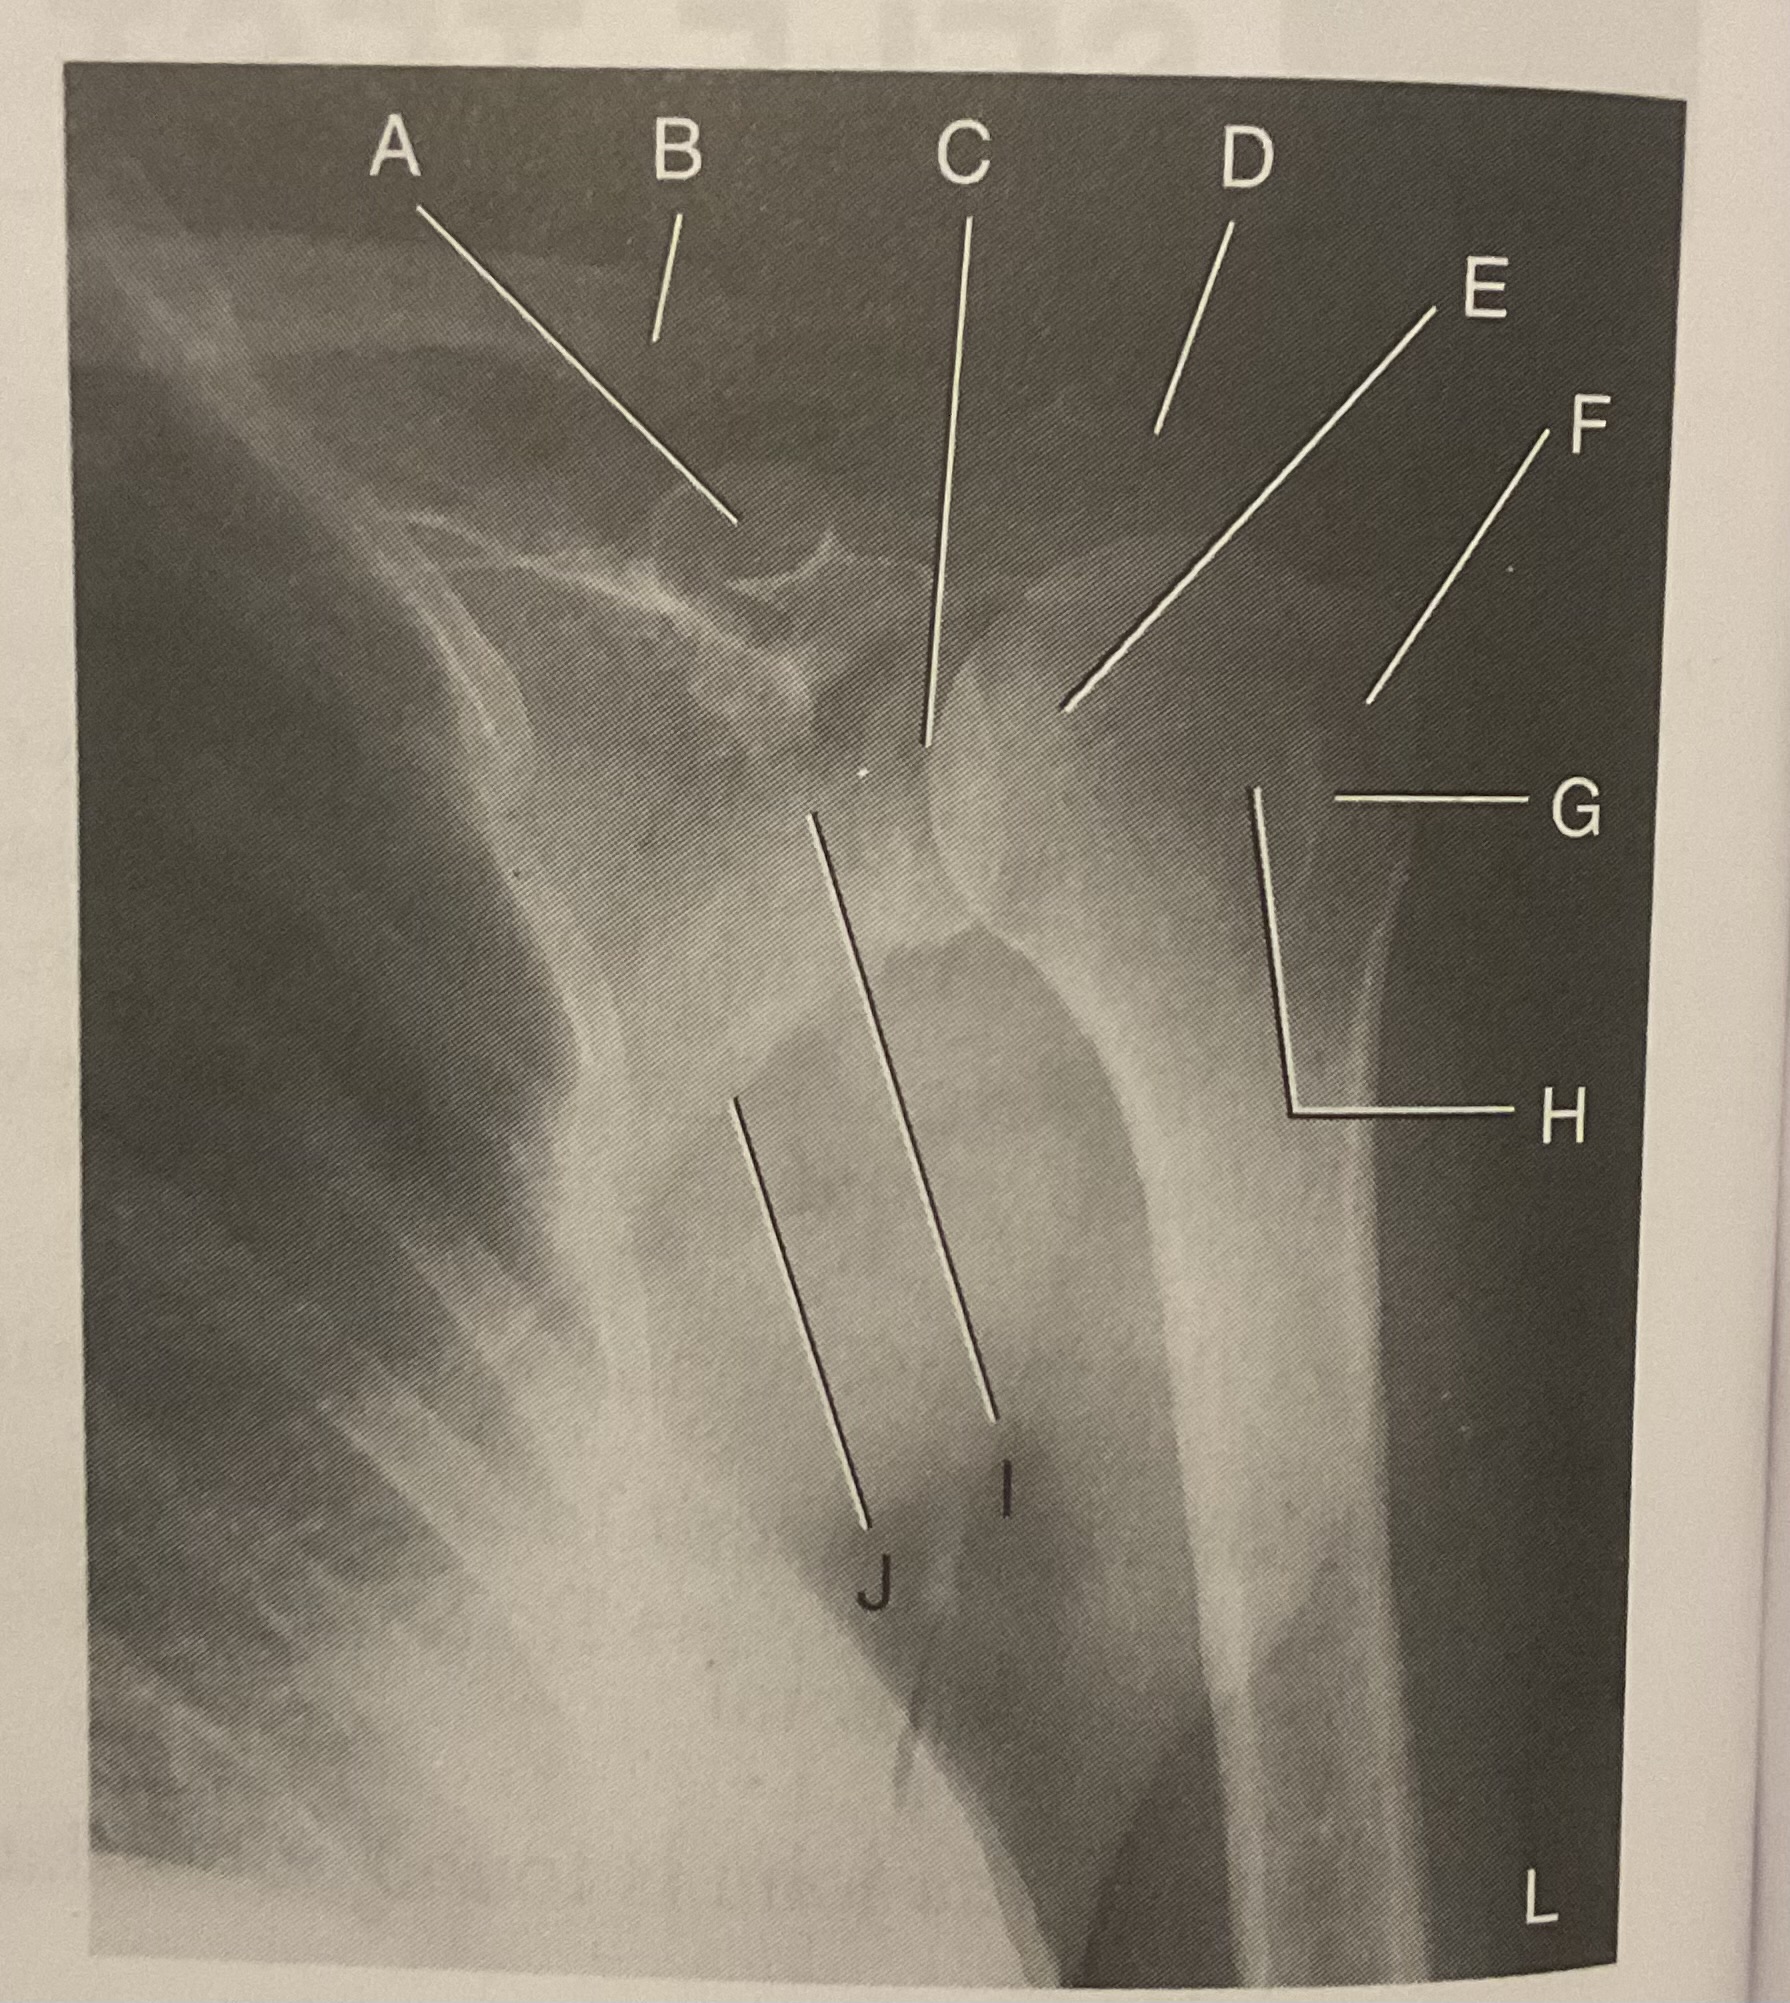

A?

Coracoid process

B?

Clavicle

C?

Scapulohumeral joint

D?

Acromion of scapula

E?

Head of humerus

F?

Greater tubercle

G?

Intertubercular sulcus

H?

Lesser tubercle

I?

Neck of scapula

J?

Lateral (axillary) border of scapula

What AP projection does this image represent?

External